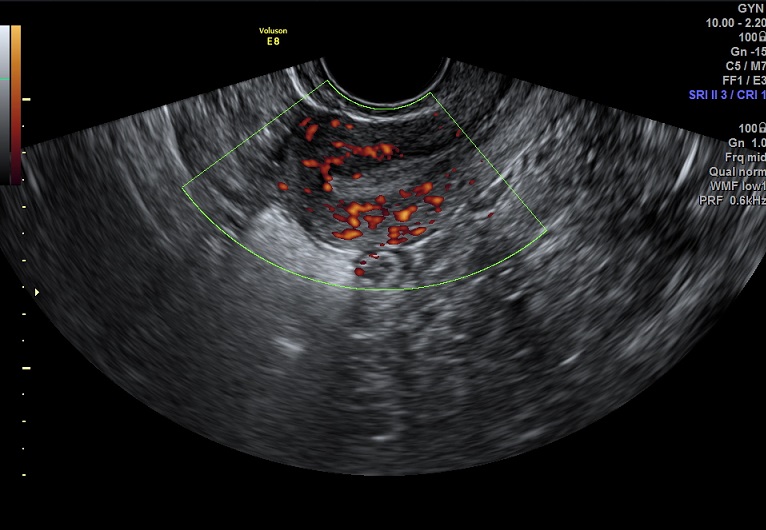

女性,24岁,原发性不孕1年余。

2015-3-10 月经第19天检查

内膜厚0.7cm

内膜血流:2级

内膜波动可见

左卵巢黄体 右卵巢囊性结构